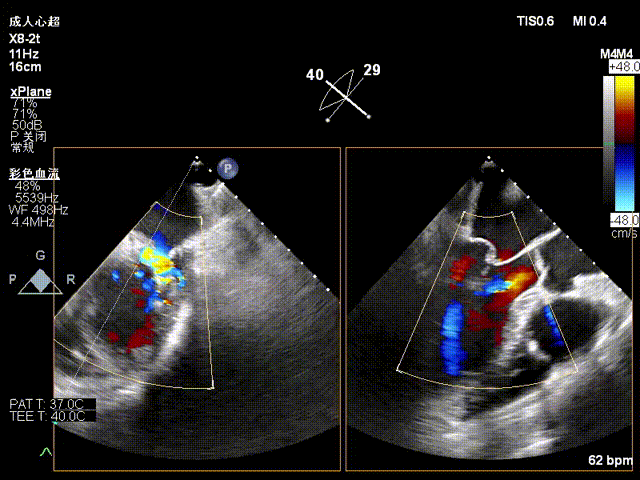

术前二尖瓣大量反流,脱垂宽度超过20mm,主要为P2区及部分P3区

第一枚瓣膜夹植入于P2P3位置,植入后内侧反流消失